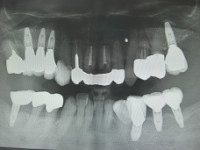

今日のオペは上顎左右1番の歯根端切除と骨補填です。

この部位の根尖には歯冠大の歯根嚢胞があり、ずっと根管治療を行ってきたのですが、根尖からの排膿が消失せずなかなか良くならなかった為に、歯根嚢胞と感染した根尖部を根こそぎ除去してしまう歯根端切除術,及び骨補填する術式を選択することになった次第です。